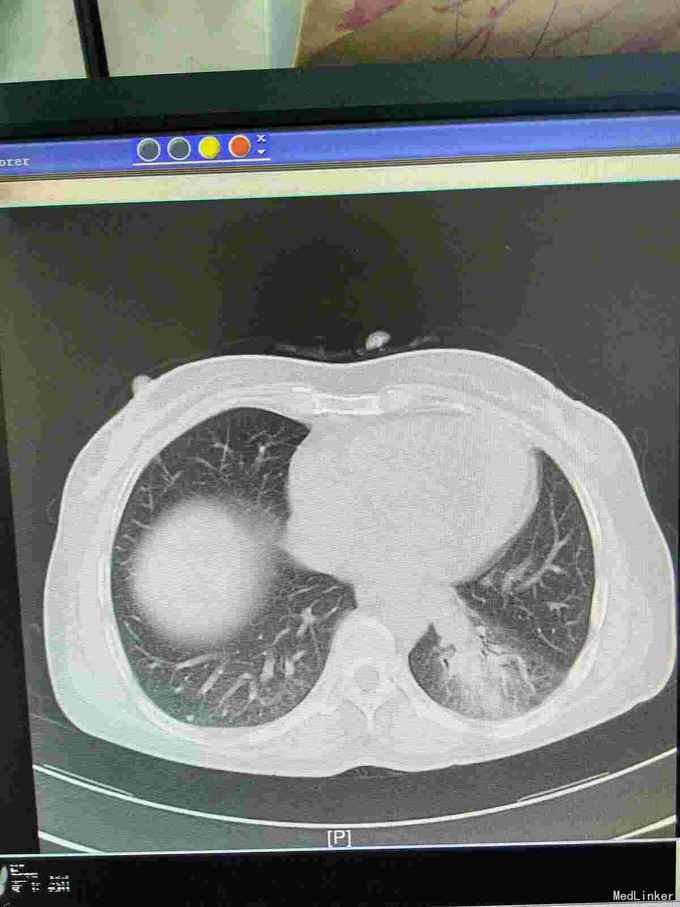

患者44岁女性,以“咳嗽咳痰间断咯血1月余”为主诉入院,入院前1月余不明显诱因出现咳嗽,呈阵发性非刺激性,咳黄白痰,每日五六口,间断咯血,色鲜红,每次10到50毫升不等,余无特殊不适,就诊当地医院摄胸部ct提示左下肺炎,予抗感染止咳化痰止血处理后症状反复,半月前复查胸部CT提示肺部阴影较前增大。

查体,神志清楚,浅表淋巴结未触及肿大,左下肺呼吸音减弱,可闻及少许湿性啰音。外院胸片示,左下肺斑片状实变阴影。

我院胸部ct增强,见左下肺病灶内见一异常供血血管,发自降主动脉,病灶周围见斑片状磨玻璃影。诊断为左肺下叶肺隔离症,转外科治疗。